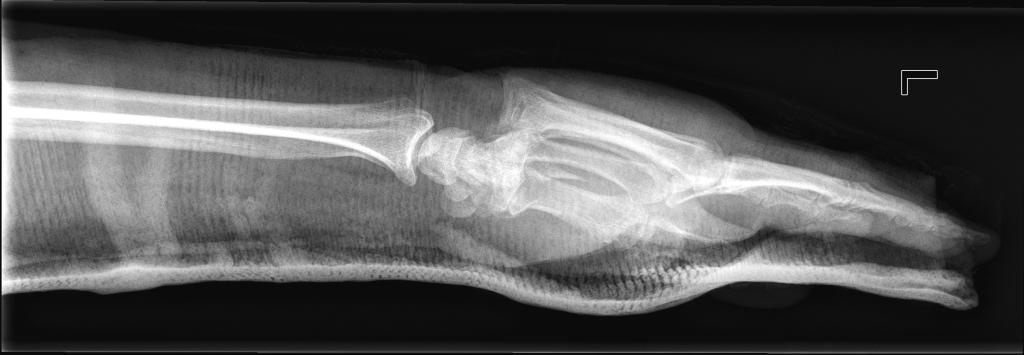

Een 70-jarige vrouw had een pijnlijke linker pols nadat zij was gevallen met haar fiets. Elders was een röntgenopname van de pols vervaardigd in anteroposterieure (AP) richting, waarop men geen afwijkingen constateerde. Vanwege de pijn kreeg zij een gipsspalk. Na 1 week zagen wij patiënte op onze polikliniek Orthopedie, waar zij aangaf nog steeds veel pijn te hebben. Omdat er elders slechts een AP-röntgenopname was gemaakt, maakten wij er een laterale opname bij (klik op de foto voor het volledig beeld).

Wat is uw diagnose?